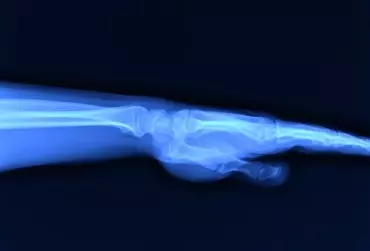

Diagnostyka różnicowa zespołów bólowych kończyny górnej - część 1

Kończyna górna w procesie ewolucyjnym człowieka z roli podporowej przekształciła się w narzędzie chwytne, zdolne do ruchów o wysokiej precyzji. Procesowi temu towarzyszyć musiały zmiany anatomii samej kończyny (pojawiły się mniej masywne kości, ale bardziej ruchome stawy z licznymi drobnymi mięśniami ręki), a także rozwój układu nerwowego, dzięki któremu człowiek może korzystać w pełni z możliwości tak doskonałego mechanizmu, jakim jest ludzka ręka. Ceną za tę ścieżkę rozwoju jest jednak zwiększone ryzyko urazów i przeciążeń kończyny górnej.

Diagnostyka różnicowa zespołów bólowych kończyny górnej - część 2

Dolegliwości bólowe w obrębie kończyny górnej mogą mieć różną przyczynę, dlatego tak ważna jest diagnostyka różnicowa. W ustaleniu prawidłowego rozpoznania pomocne jest tradycyjne badanie radiologiczne, które pozwala na wykrycie wielu patologii, takich jak urazy, zmiany zwyrodnieniowe, przeciążeniowe, choroby metaboliczne, zapalne i nowotwory, choć ma też swoje ograniczenia.